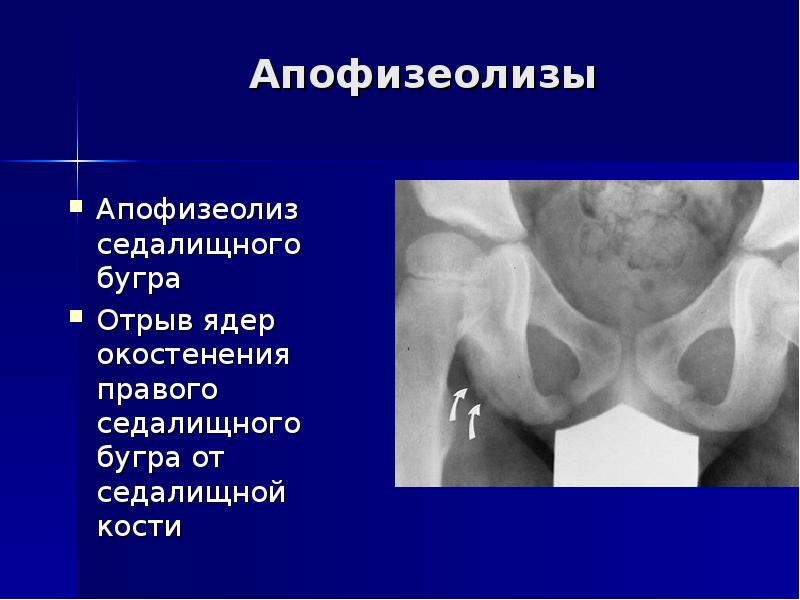

26. Апофизеолизы

Апофизеолиз

седалищного бугра

Отрыв ядер

окостенения

правого

седалищного бугра

от седалищной

кости

Апофизеолизы

Апофизеолиз седалищного бугра

Отрыв ядер окостенения правого седалищного бугра от седалищной кости